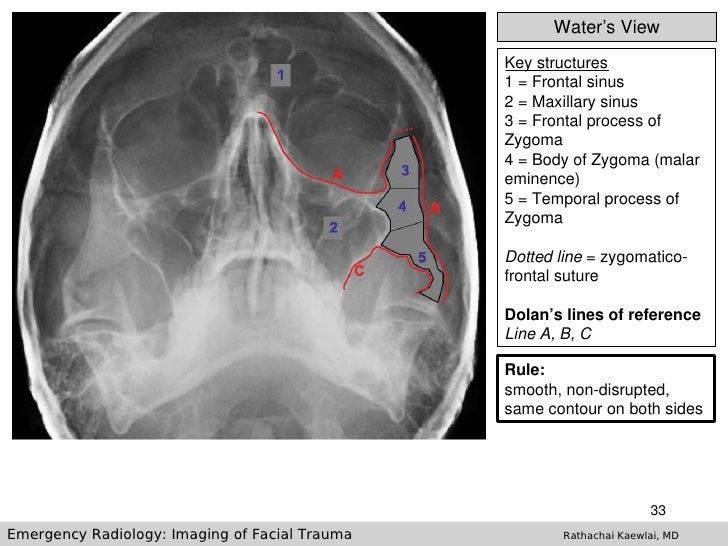

Basic Anatomy Views -importance And Positioning Interpretation Skull

Basic anatomy Views -importance and positioning Interpretation Skull www.slideshare.net

Imaging Of Facial Trauma Part 1

Imaging Of Facial Trauma Part 1 www.slideshare.net

sinus maxillary